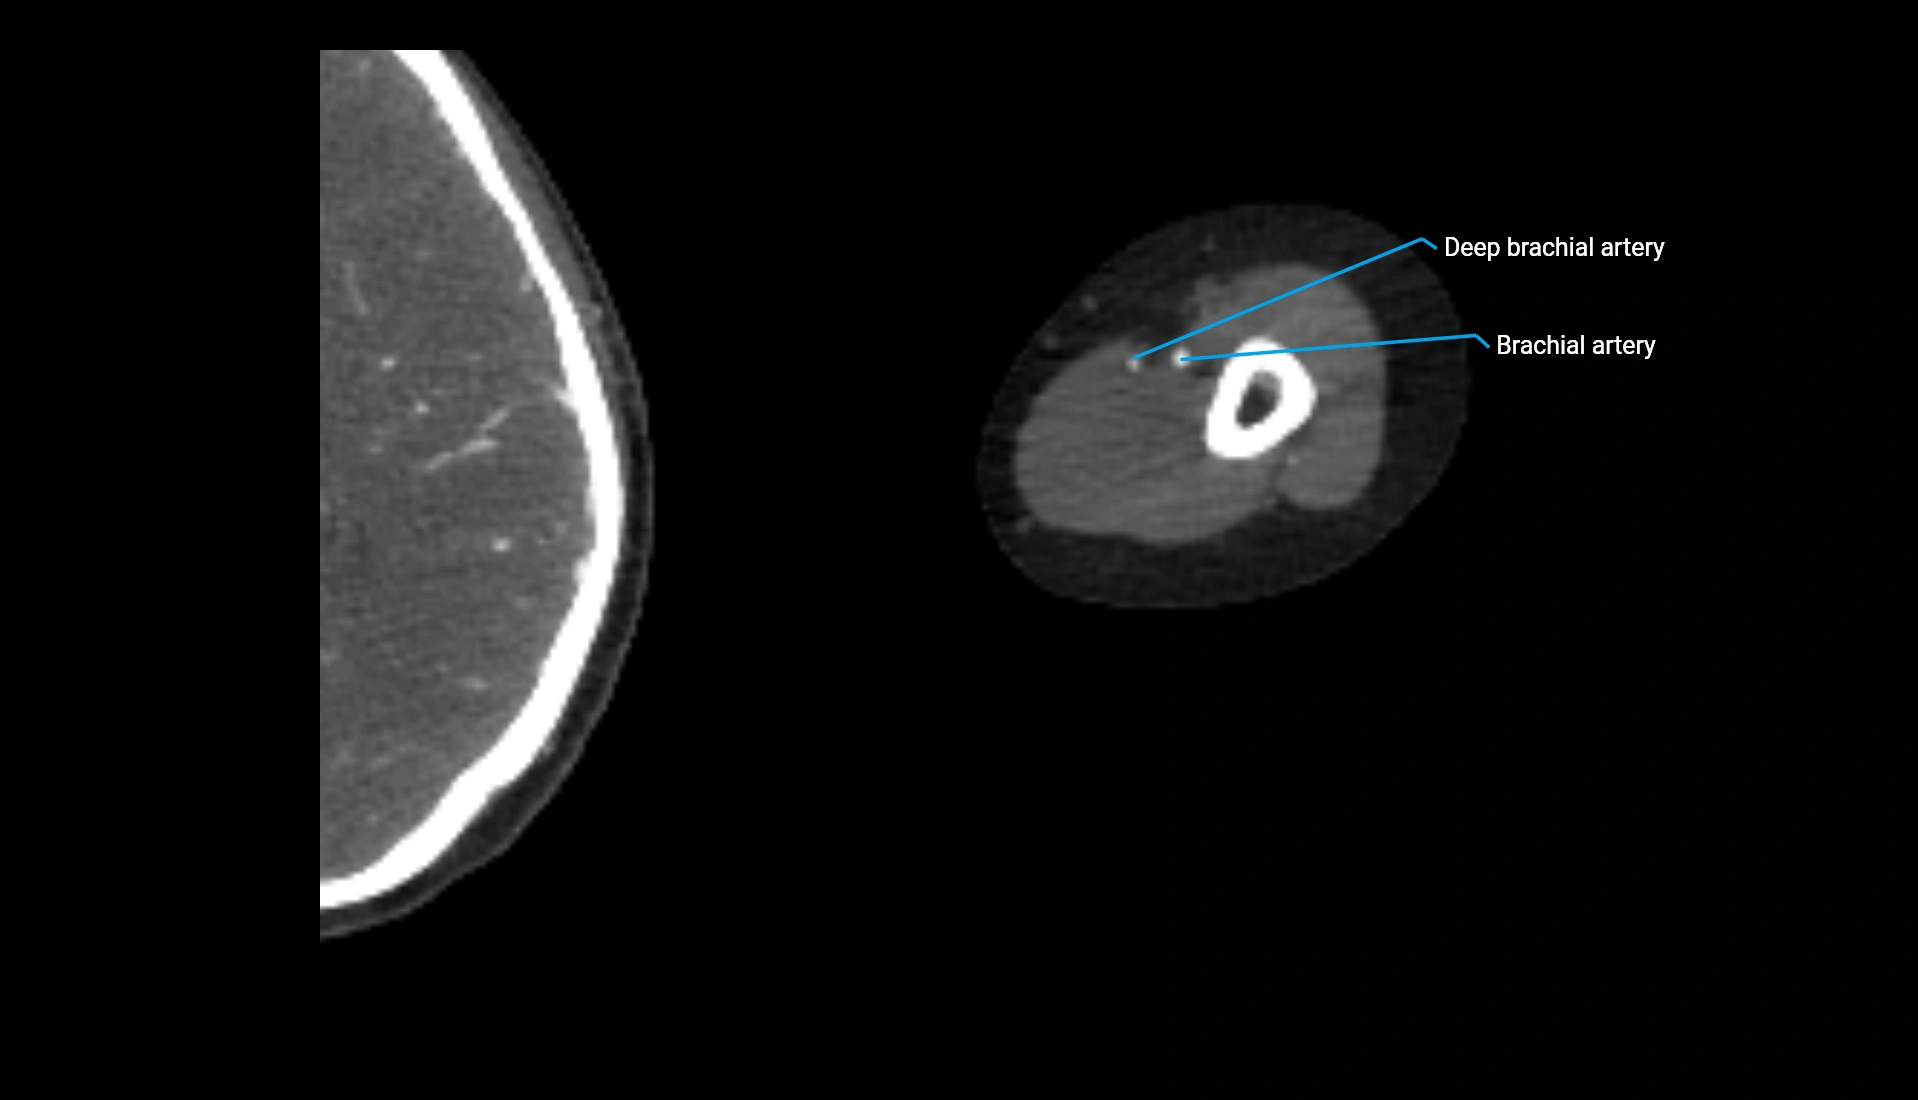

CT Appearance

Non-Contrast CT:

• Cortex: High-density, sharply defined

• Subchondral bone: Dense cancellous matrix

• Articular surface: Smooth concave contour articulating with the capitellum

• Excellent for evaluating bone integrity, alignment, and subtle fractures

Post-Contrast CT:

• Bone: No enhancement

• Joint capsule and synovium: Mild enhancement outlining the joint

• Improves contrast between soft tissues and bony margins

• Useful in detecting subtle joint abnormalities or postoperative changes